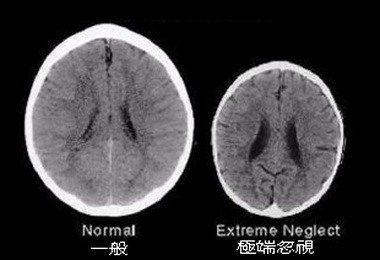

母親對每個剛出生的孩子來說,不僅實質的提供了營養來源「母乳」,更多的是無形的「母愛」...